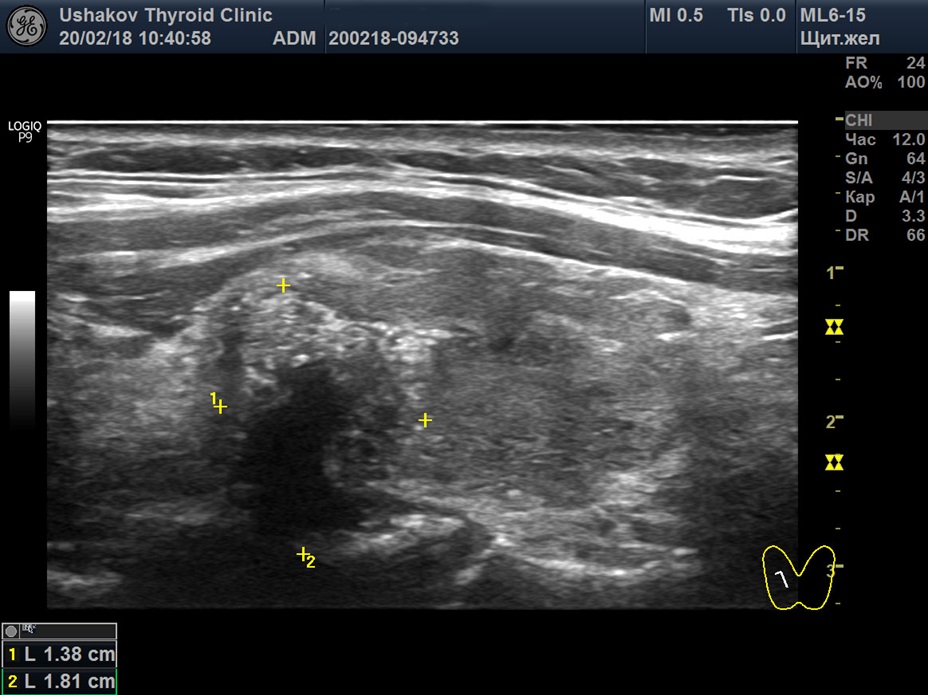

Но все специалисты опирались на одни и те же признаки рака. Читайте об ультразвуковых признаках рака узлов в специальной статье сайта нашей Клиники. Пример ультразвуковых признаков показан на

рисунке 5.

Рисунок 5 Узел верхней (краниальной) части правой доли щитовидной железы (ограничен желтыми метками). Признаки рака узла: 1) неправильная форма, 2) неравномерный край узла, местами прерывистая граница, 3) значительно гипоэхогенная (темная) зона внутри узла, постепенно переходящая в остальную ткань, 4) микрокальцинаты. 5 уровень по ACR TI-RADS (10 баллов) или 5 категория по EU TI-RADS.